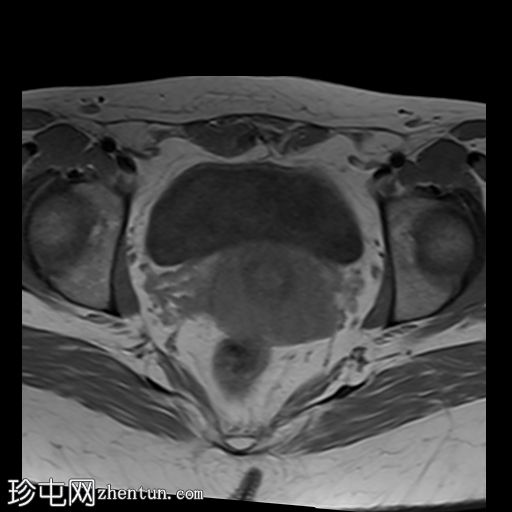

轴位

T2加权像

MRI特征符合剖宫产术后瘢痕子宫内膜异位症,表现为特征性T1高信号伴T1FS持续存在,T2低信号伴内部高信号灶,病灶边缘浸润于腹前壁肌肉内,以及对比增强。

该病灶累及腹白线并浸润腹直肌,主要位于中线左侧,耻骨联合及结节处腹直肌起点上方。

未见明确的腹膜内或皮下软组织侵犯。

双侧卵巢增大,内含多个小卵泡(每侧卵巢10-12个或更多)。